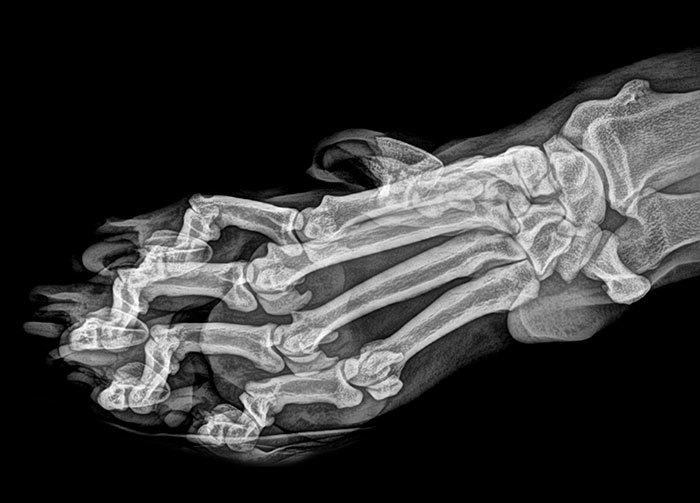

文章插图

X射线的脚在细高跟鞋